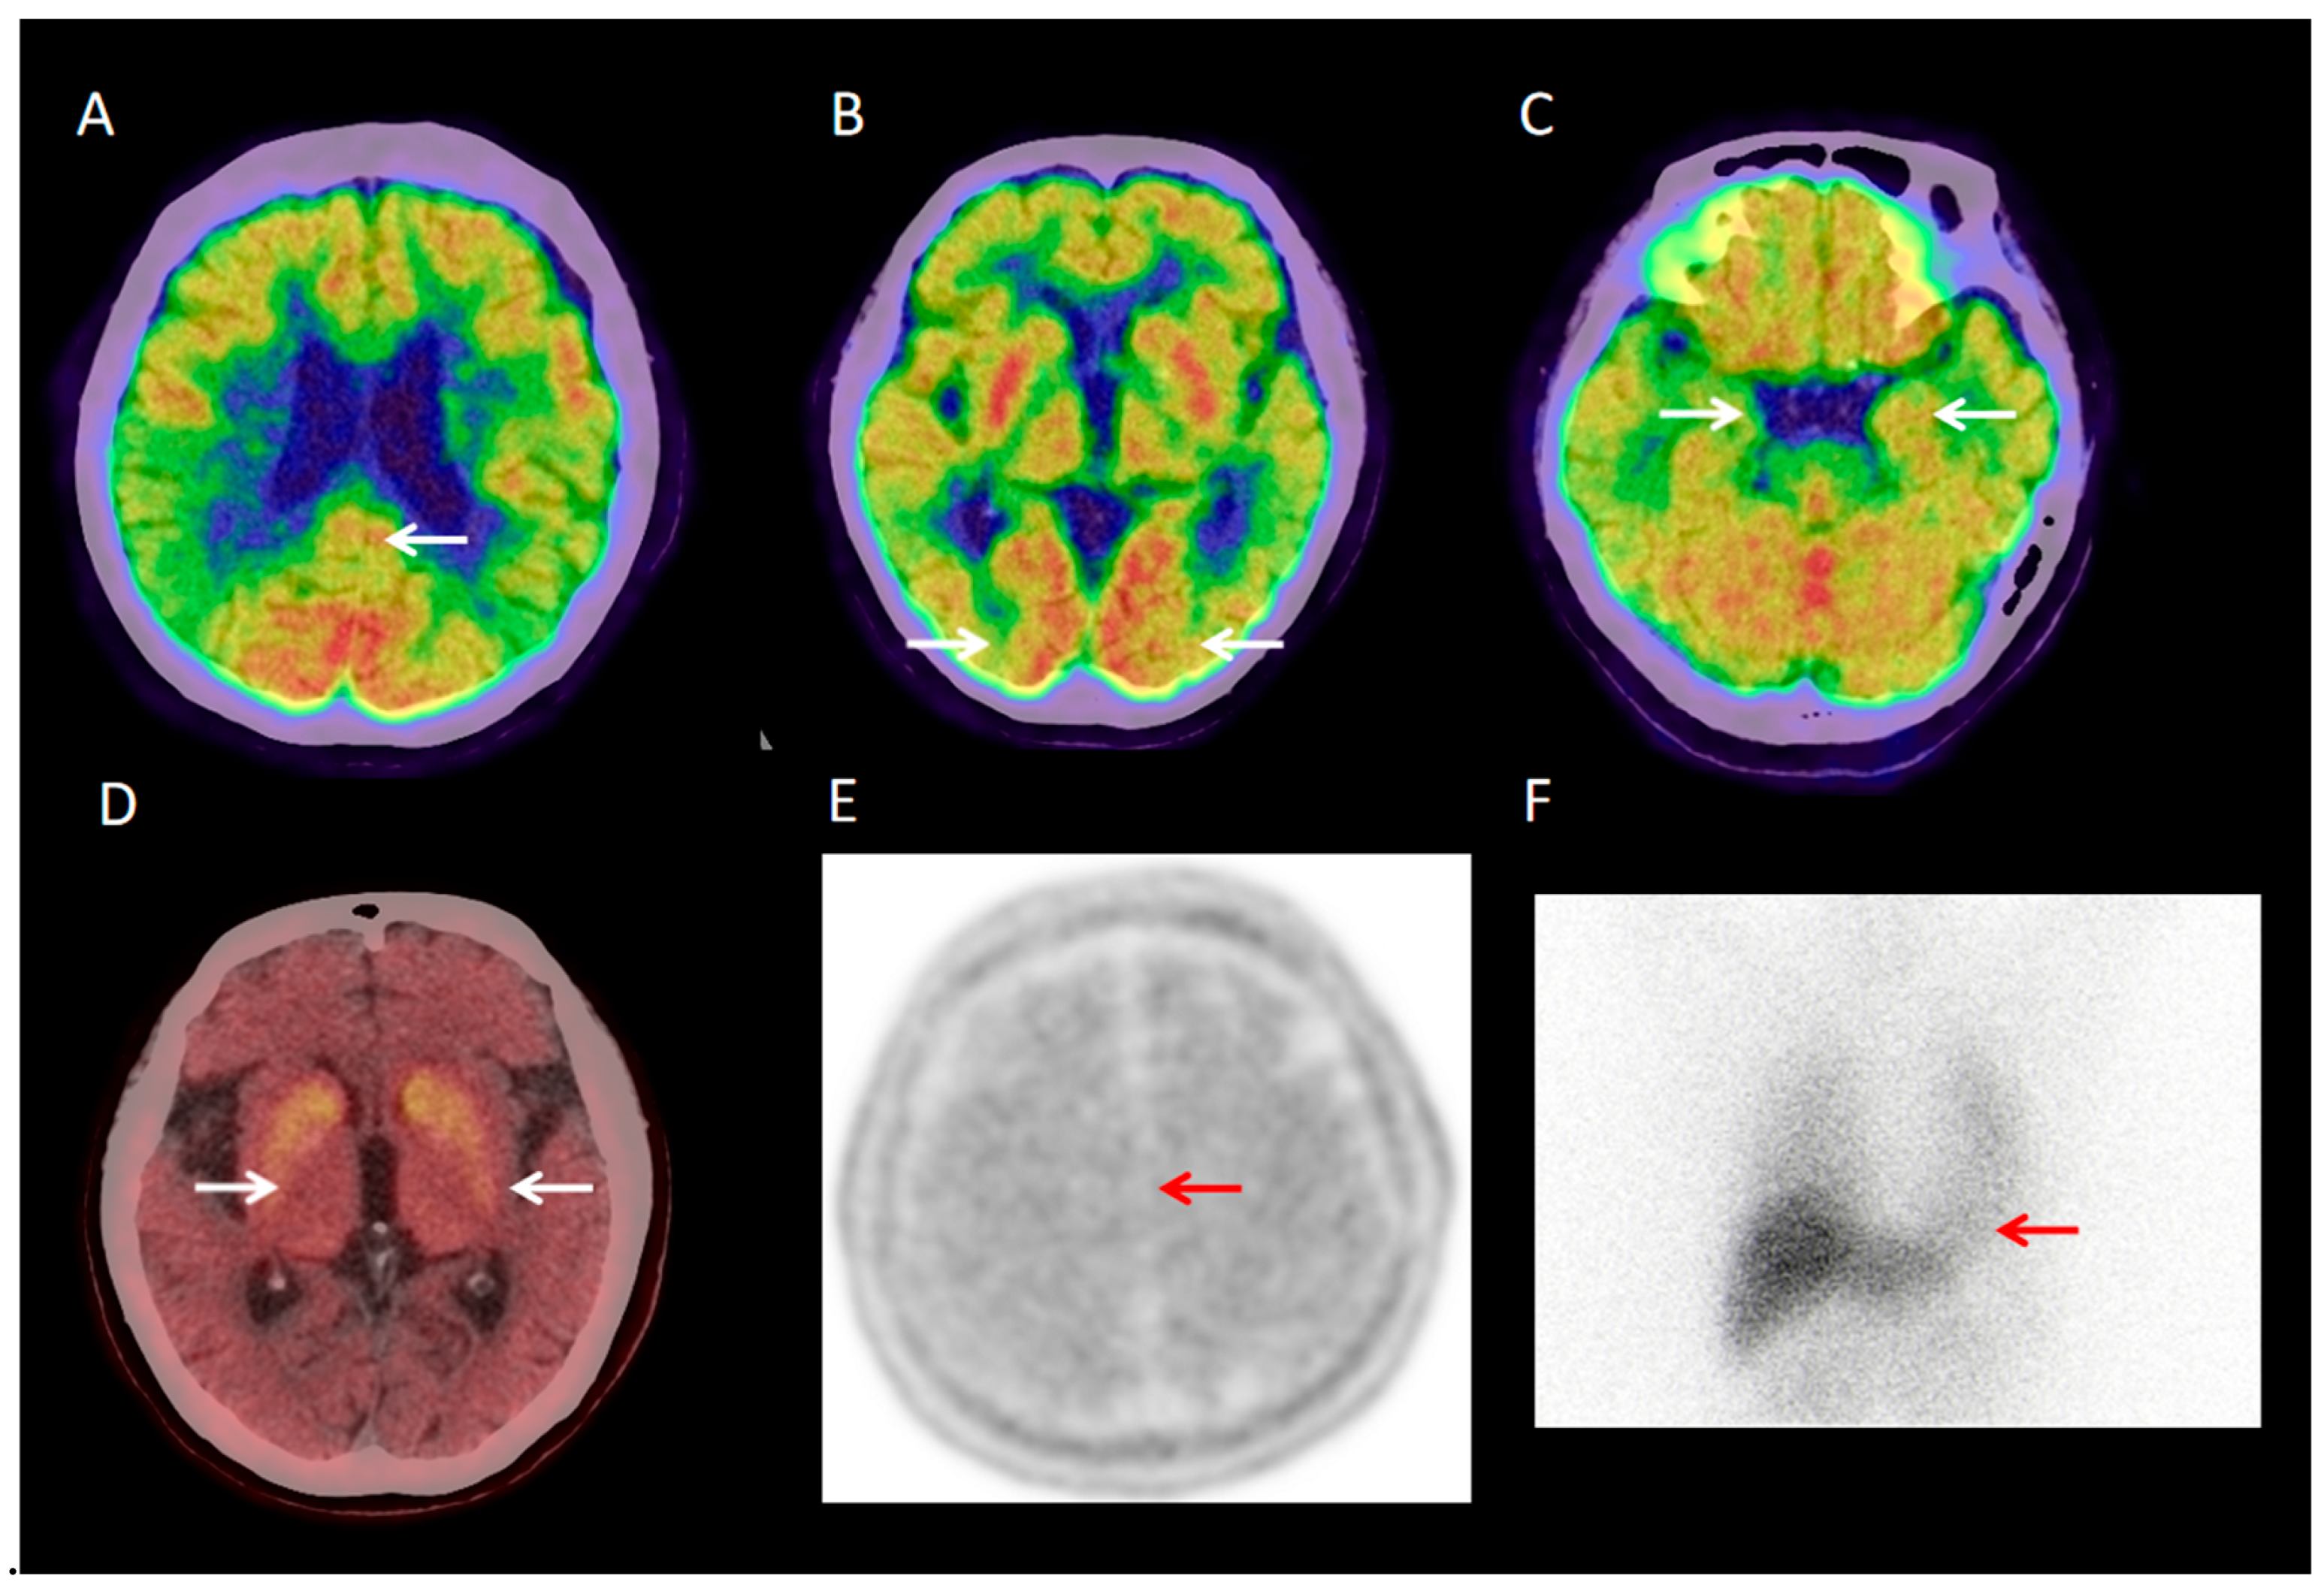

3.2.1. Visual Analysis of 18F-FDG PET/CT

3.2.6. Visual Analysis of 18F-FP-CIT PET/CT

3.2.7. Visual Analysis of 131I-MIBG SPECT

3.2.8. Visual Analysis of 18F-PM-PBB3 PET/CT